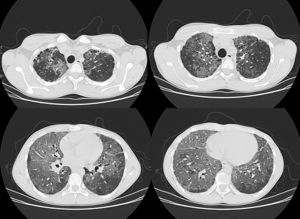

Upon admission to the pulmonology unit, the patient had dyspnea grade I–II. Physical examination revealed good coloration of the skin and mucous membranes, and finger clubbing. Baseline O2 saturation was 93% and good vesicular breath sounds were perceived upon auscultation, with no added noises. Spirometry indicated FEV1: 44%, FVC: 47%, FEV1/FVC: 79, MMEF: 29%, although patient cooperation was incomplete. The chest X-ray showed an extensive bilateral alveolointerstitial pattern with multilobar involvement. The examination was completed during hospitalization with high-resolution computed tomography (HRCT), in which marked alteration of the lung parenchyma was observed, with large ground-glass fields in all lobes, but predominantly basal. There was overlapping septal thickening, forming a crazy-paving pattern (Fig. 1). Furthermore, honeycombing areas were visible in the subpleural lung parenchyma at the level of both upper lobes, although predominantly in the right side.

The most common HRCT radiological findings in LP4,5 are the presence of condensation with low attenuation coefficient (between −75 and −35 UH) that is very specific and prevalent in endogenous LP,1 ground-glass opacities, crazy-paving pattern, and presence of centrilobular opacities. In addition, lung involvement is mainly basal.4

The crazy-paving pattern was initially described in alveolar proteinosis, although it was later shown to appear in several processes,4 including sarcoidosis, non-specific interstitial pneumonia, organizing pneumonia (both cryptogenic organizing pneumonia and bronchiolitis obliterans organizing pneumonia) pulmonary infections (mainly viral and mycoplasma), malignancies such as bronchoalveolar carcinoma, hemorrhage, pulmonary edema and LP.